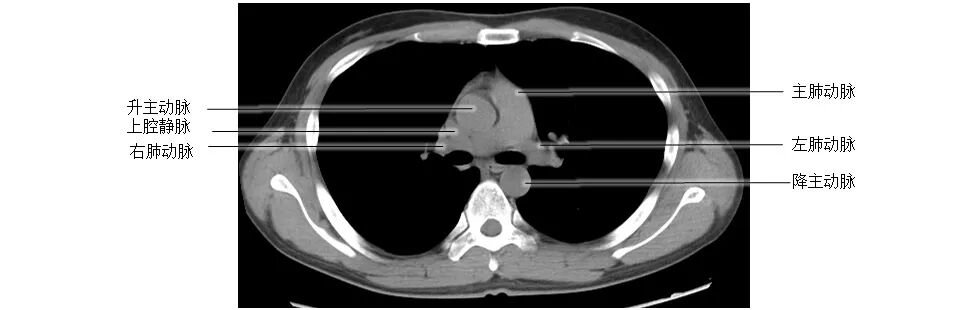

正常胸部CT影像是从横断面显示解剖和病变,可显示的结构包括胸廓、气管和支气管、肺、胸膜、纵隔和膈,CT的重建图像可从各个角度显示胸部解剖情况。不论采用何种图像显示方式,把握基本解剖结构都是必不可少的,一起学习胸部CT肺窗和纵隔窗的正常解剖。

胸部CT纵膈窗